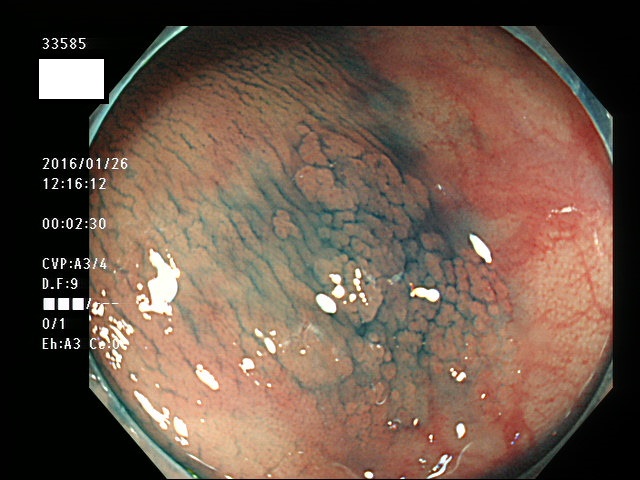

上記100名より抽出した平坦・陥凹型腺腫(=癌化の危険が高いが見落としやすい病変)の内視鏡写真

33500 33501 33505 33507 33508 33509 33510(SSA/Pのみ) 33511 33512 33514 33517 33519 33523 33528 33529 33530 33535 33537 33538 33539 33540 33544 33546 33547 33548 33549 33550 33552 33553 33555 33558 33559 33562 33563 33567 33571 33576 33578 33580 33581 33583 33585 33586 33587 33589 33590 33594 33595 33596 33599 ・・・・・・の50名